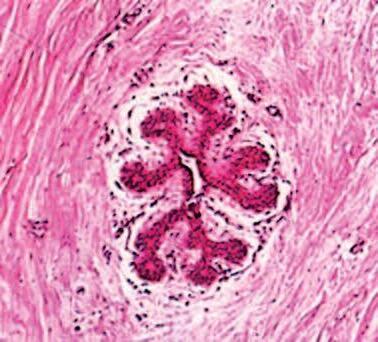

Immagine al microscopio di cellule leucemiche. Le sfere rosse del pacmen rappresentano gli enzimi collagenasi.

La foto nella pagina a fianco mostra una sezione trasversale al microscopio del fegato di un paziente con ‘leucemia linfatica’. Ciascuno dei piccoli puntini viola nella foto è un globulo bianco (in questo caso linfocita) che ha invaso il tessuto del fegato (aree rosa).

Considerando l’enorme quantità di questi puntini viola e il numero di enzimi che assimilano il collagene che ciascuno produce, è facile prevedere l’ingente distruzione del tessuto connettivo e il danno apportato all’organo da questo tipo di cancro.

Immagine al microscopio della leucemia linfatica

Globuli bianchi affetti di cancro (linfociti) invadono il fegato L’enorme quantità di collagenasi prodotte da queste cellule distruggono l’organo e causano insufficienza epatica.